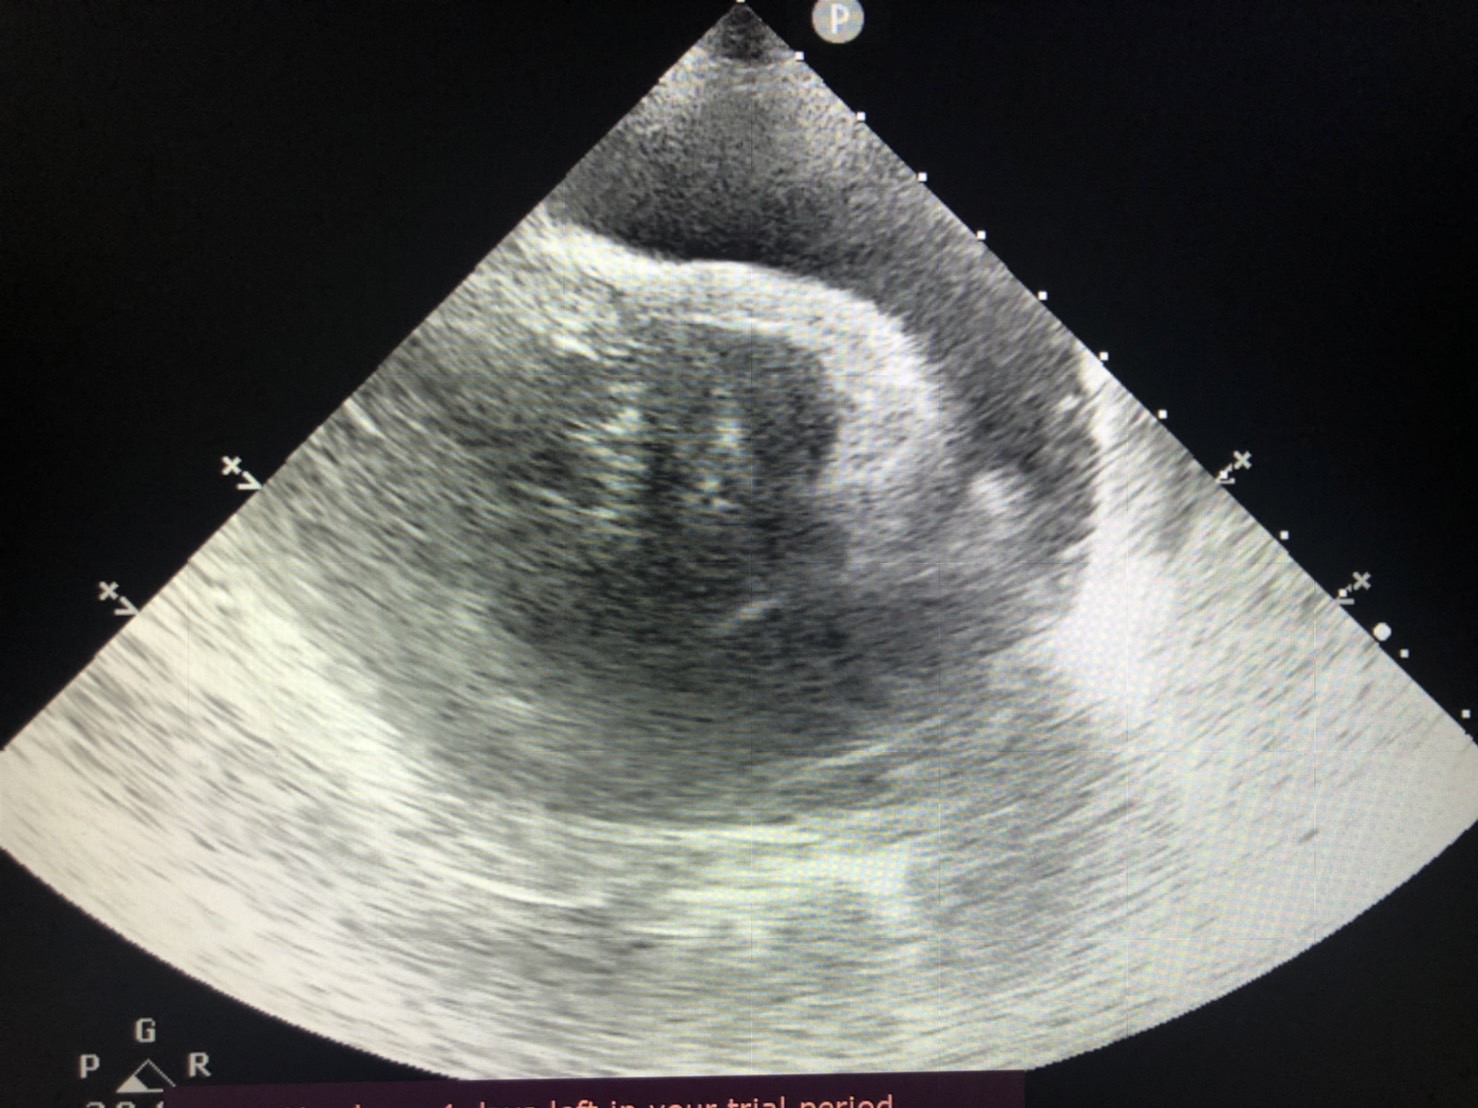

• 心包囊積液

心包囊積液